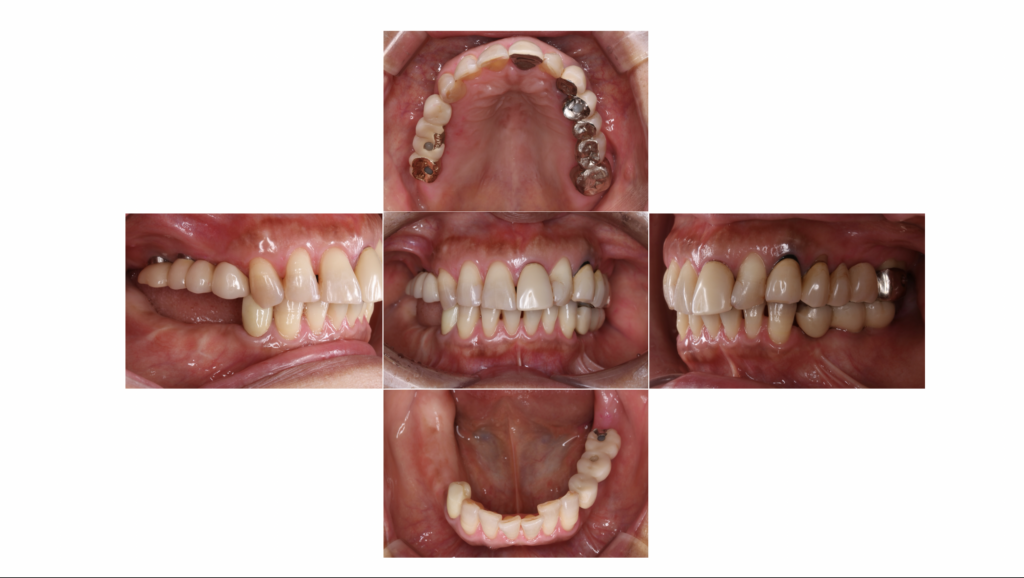

今回ご紹介する症例は、他の部位にはすでにインプラントが入っている一方で、右下には入れ歯が入っていた患者様の治療例です。

インプラントと入れ歯が混在した状態は、一見問題なく過ごせているように見えても、

長期的には噛み合わせのバランスが崩れ、周囲の歯や被せ物に負担がかかることがあります。

今回は、そうした将来的なリスクを踏まえ、

右下に3本のインプラント治療を行い、口腔内全体の安定を図った症例となります。

初診時の状態と主訴:

患者様は、

「右下の入れ歯と、すでに入っているインプラントとの噛み合わせが気になる」

というお悩みで当院を受診されました。

治療計画を立てるにあたり、患者様に現在のお悩みや、将来的な希望について丁寧にお伺いしました。

患者様のご希望

1. しっかり噛める状態にしたい

2. 入れ歯ではなく、できれば固定式の治療にしたい

3. 今後、他の歯をできるだけ長持ちさせたい

これらを踏まえ、以下の治療計画をご提案しました。

治療計画

右下臼歯部にインプラント3本を埋入

・既存のインプラントや噛み合わせとの調和を考慮した補綴設計

・口腔内全体のバランスを重視した治療

入れ歯を作り直すという選択肢も含めて説明しましたが、長期的な安定性と、他の歯を守ることを優先し、

インプラント治療を選択されました。